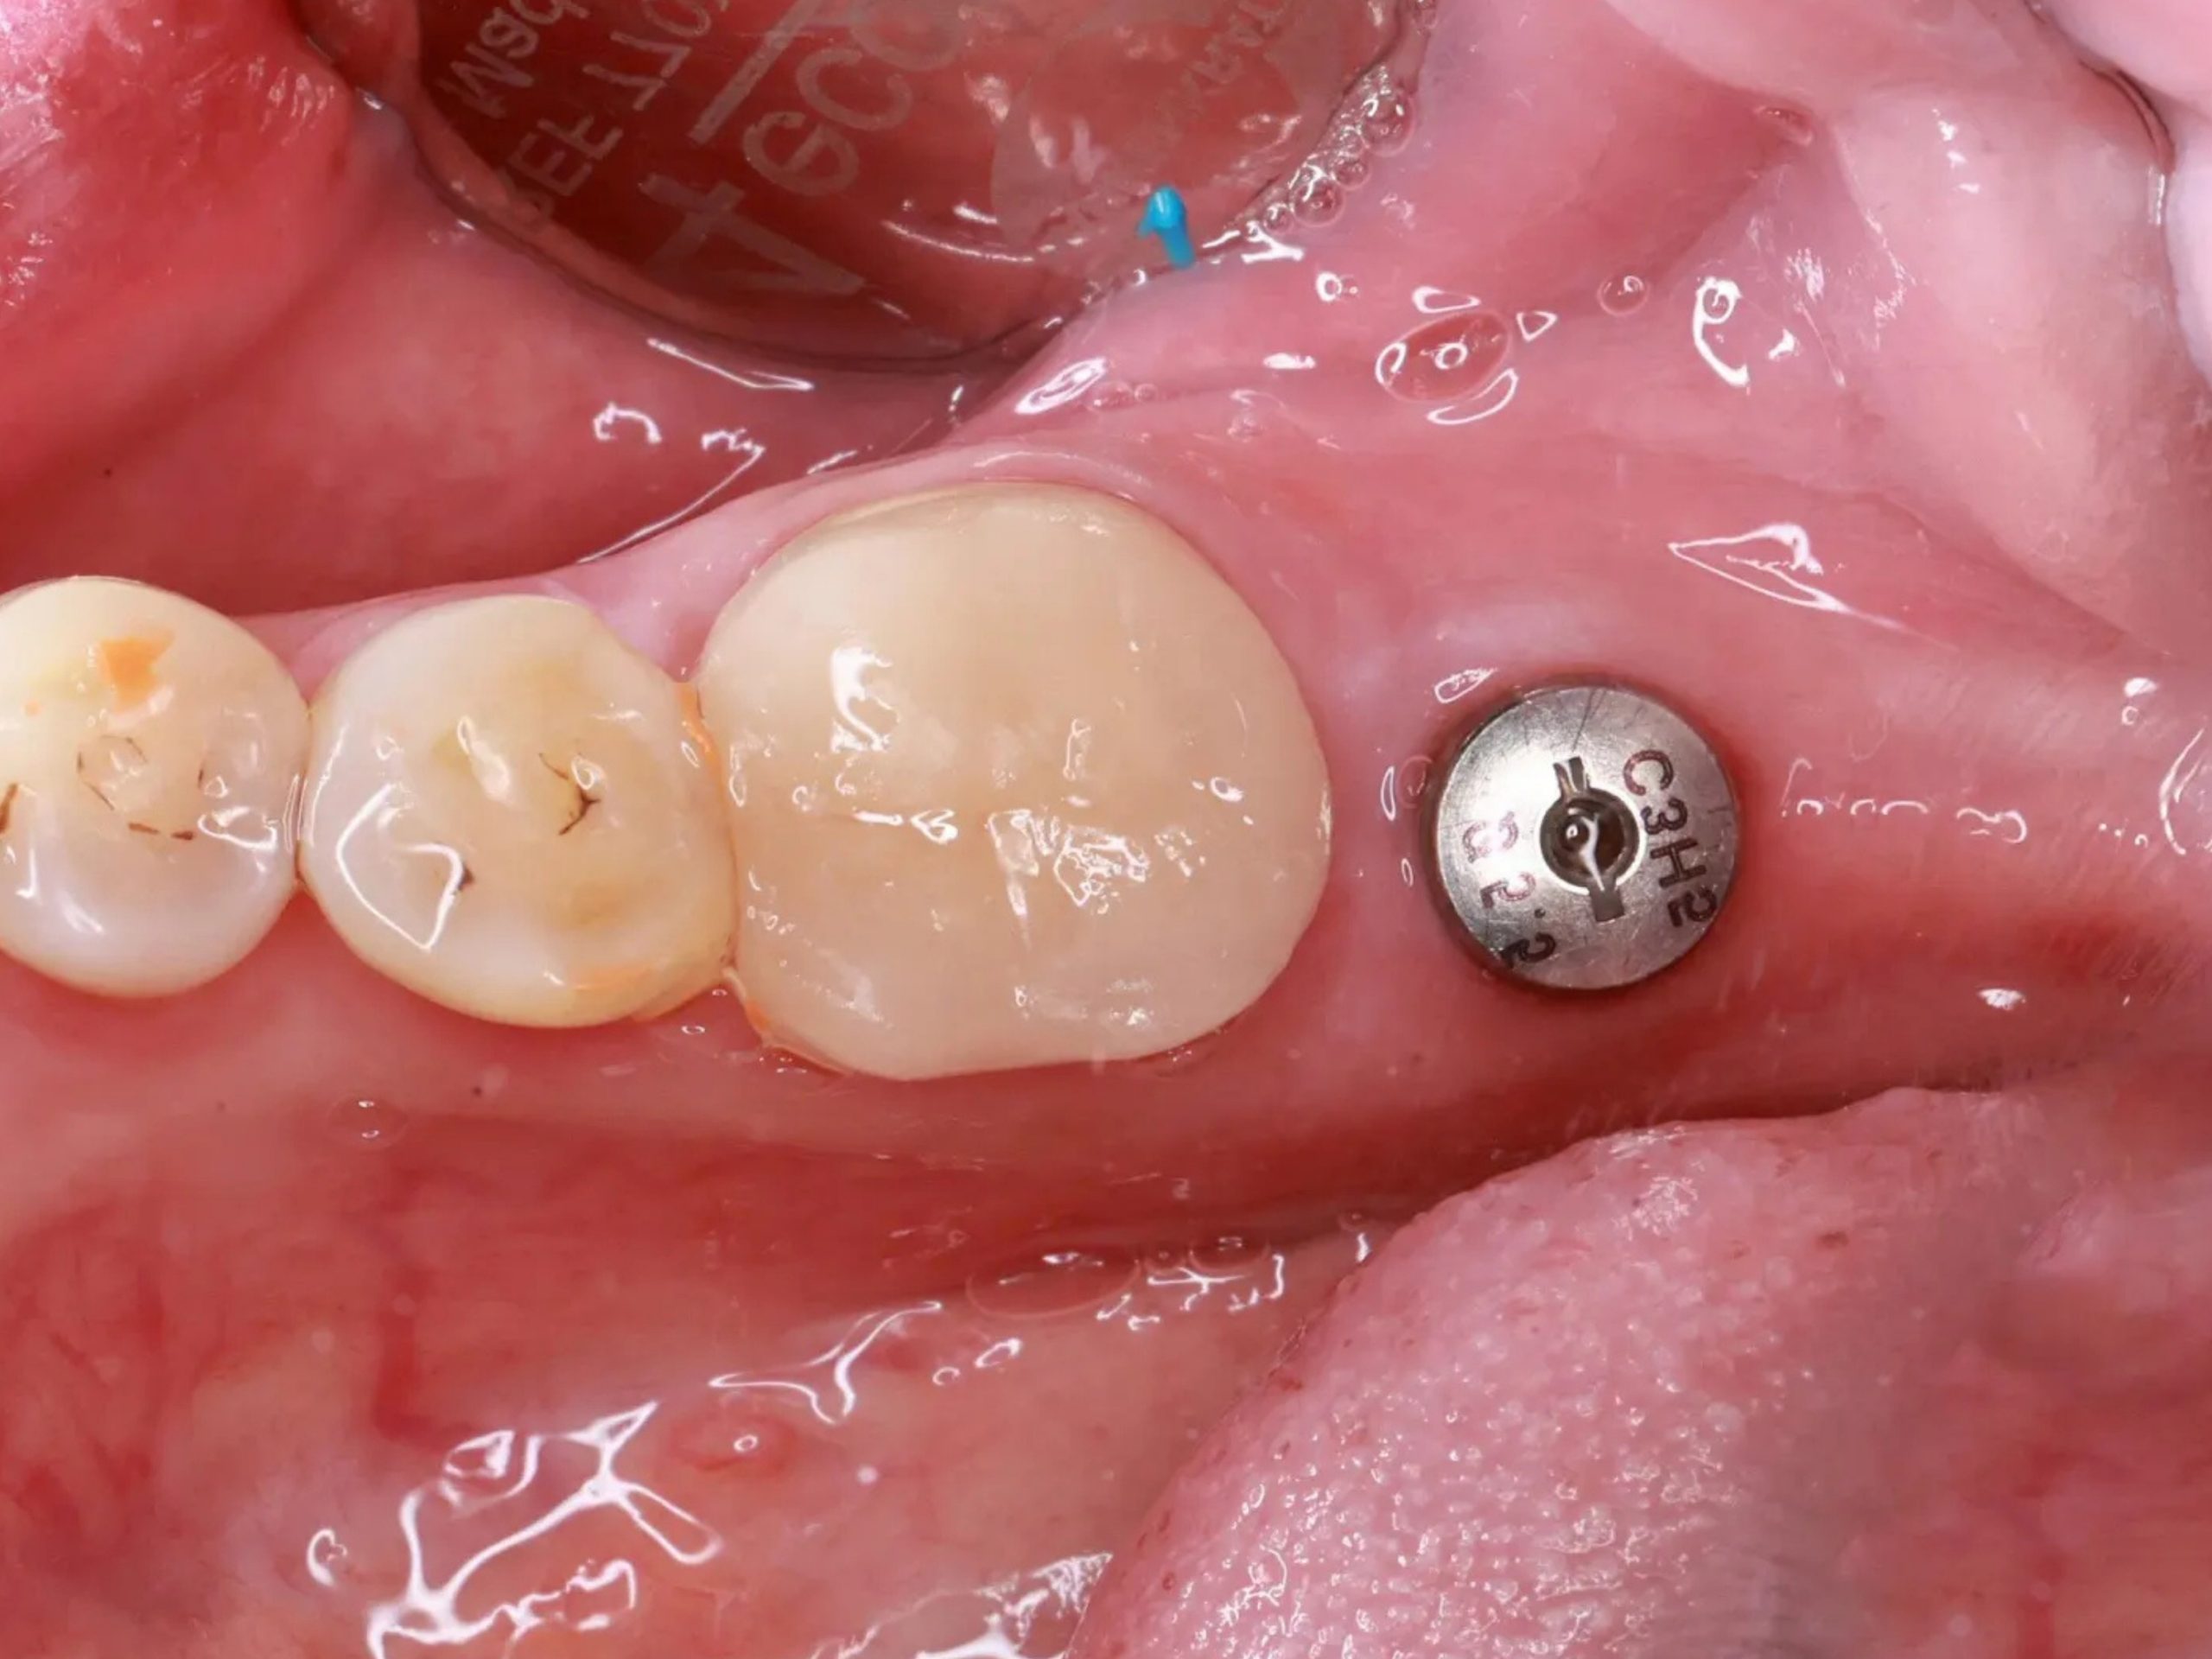

Trồng răng Implant (hay cấy ghép Implant) không chỉ đơn thuần là thay thế răng đã mất mà còn mang lại nhiều giá trị lâu dài cho sức khỏe và chất lượng cuộc sống. Implant phục hồi một chiếc răng hoàn chỉnh bằng cách cấy trụ Titanium vào xương hàm rồi gắn mão sứ lên trụ. Cụ thể, những lợi ích nổi bật có thể kể đến:

Nhờ những ưu điểm trên mà cấy ghép Implant được các bác sĩ chuyên gia khuyến nghị cho người mất răng như một giải pháp phục hồi răng mất toàn diện và bền vững.